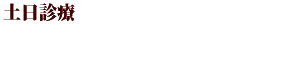

歯肉炎

歯と歯ぐきの間にある溝にプラーク(歯垢)が溜まり、歯ぐきに炎症を起こします。プラークと炎症によって歯周ポケットができますが、この段階ではまだ、歯を支える歯槽骨は悪くなっていません。